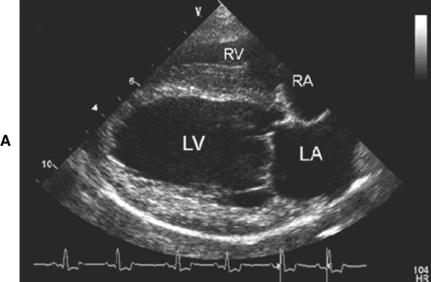

Ekokardiyografi

Kalp hastalıklarında tanının en kıymetli araçlarından biri kuşkusuz ki ekokardiyografi ile kalbin iç yapıları, duvar kalınlıkları ve kapak hareketleri ile çevre dokuları hakkında detaylı görüntüler alabilmek; kan akım dinamiklerini incelemektir. Bu amaçla özel problu ve yazılımlı ultrasonografi cihazları ile hastalarda herhangi bir yatıştırıcı yada anestesi uygulamadan yarım saat gibi kısa bir sürede muyaenelerini gerçekleştiriyoruz. Elde edilen sonuçları her ırk ve vücut ağırlığına uygun referans tablolarınca değerlendirerek hastalığın kesin tanısını oluşturuyoruz.